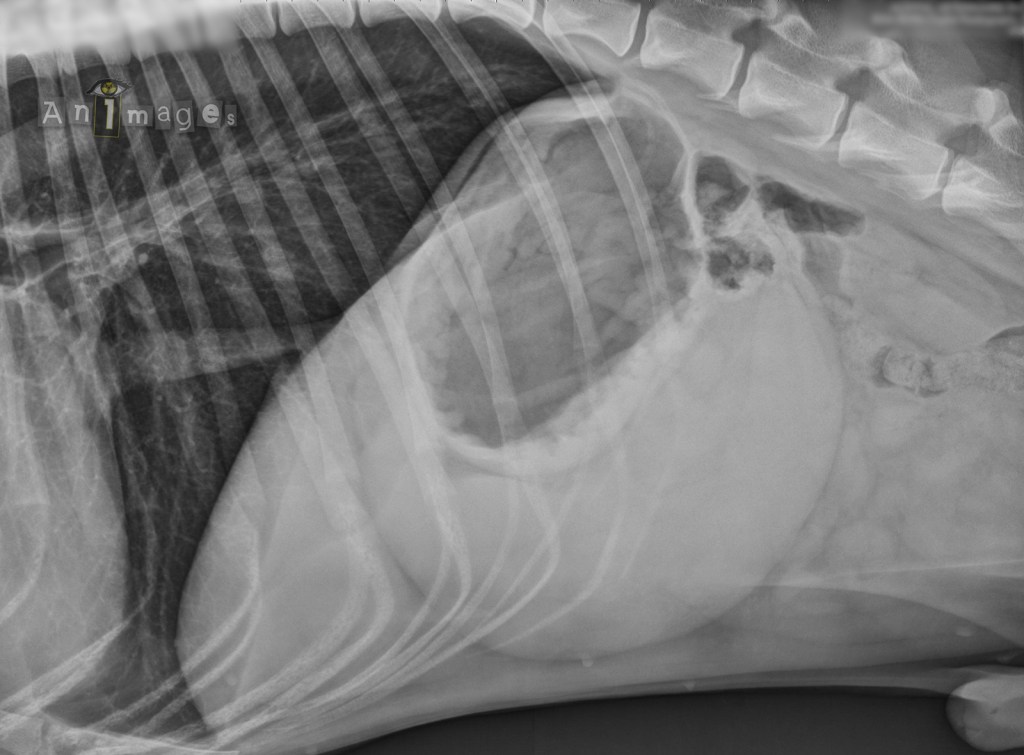

Latérale droite 1